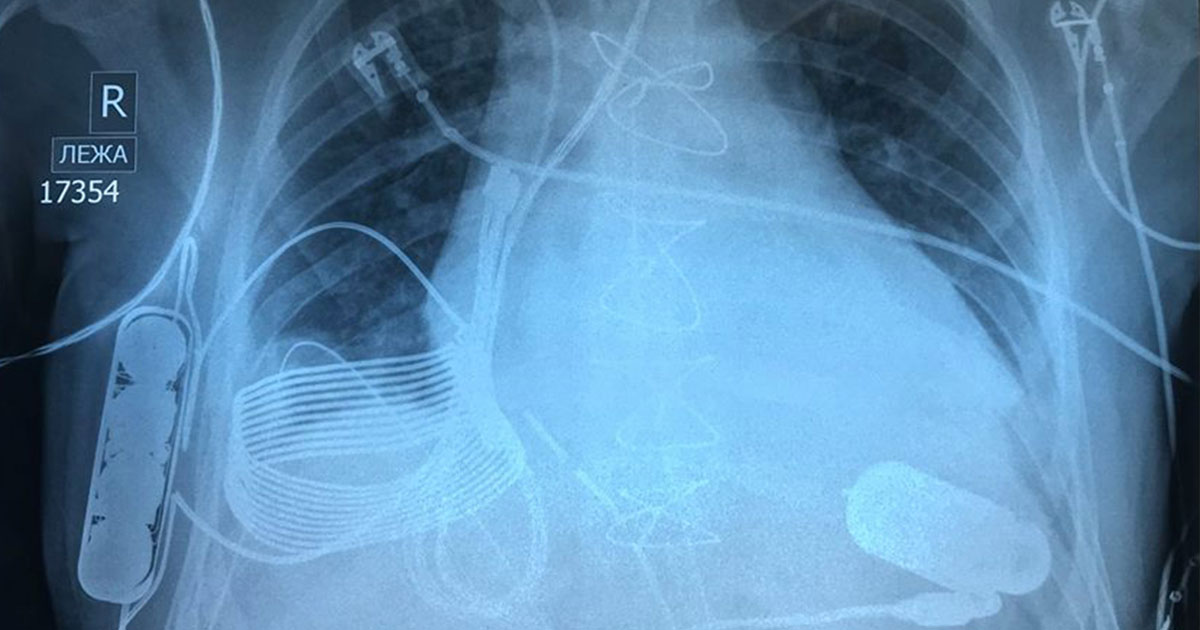

The 24-year-old man was experiencing end-stage heart failure when doctors in Kazakhstan implanted a VAD into him in December. But the device in Tursunov’s chest is unlike any other — it charges wirelessly, eliminating one of the biggest points of failure in a device that cannot afford to fail.

But Tursunov’s VAD doesn’t need that power cord thanks to a charging system created by Israeli tech company Leviticus Cardio.

The system comprises a receiver inductive coil, a battery, and an internal controller, all implanted in Turnsunov’s chest. The device gets about eight hours of use out of a single charge, and when Turnsunov needs to recharge it, he slips on a vest containing an external coil that charges the inner coil electromagnetically.

A wrist monitor helps Turnsunov keep track of his VAD, and if the battery gets too low or the device experiences some other major malfunction, an internal vibration alarm is triggered. Just in case something goes wrong with the wireless charging system, Turnsunov does have a wired back-up option, but he hasn’t needed to use it once since his surgery.